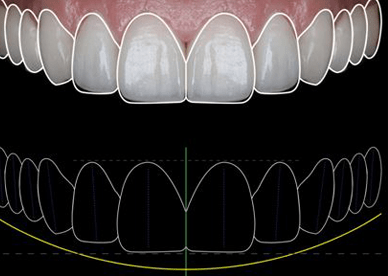

Como hemos hablado en varios post anteriores, un implante dental es una solución fija para reemplazar un diente perdido. Un implante cementado significa que la corona cerámica (el diente visible) está permanentemente unida al pilar del implante con cemento dental. Esto crea una apariencia natural y continua (sin agujeros visibles de tornillo) y una […]